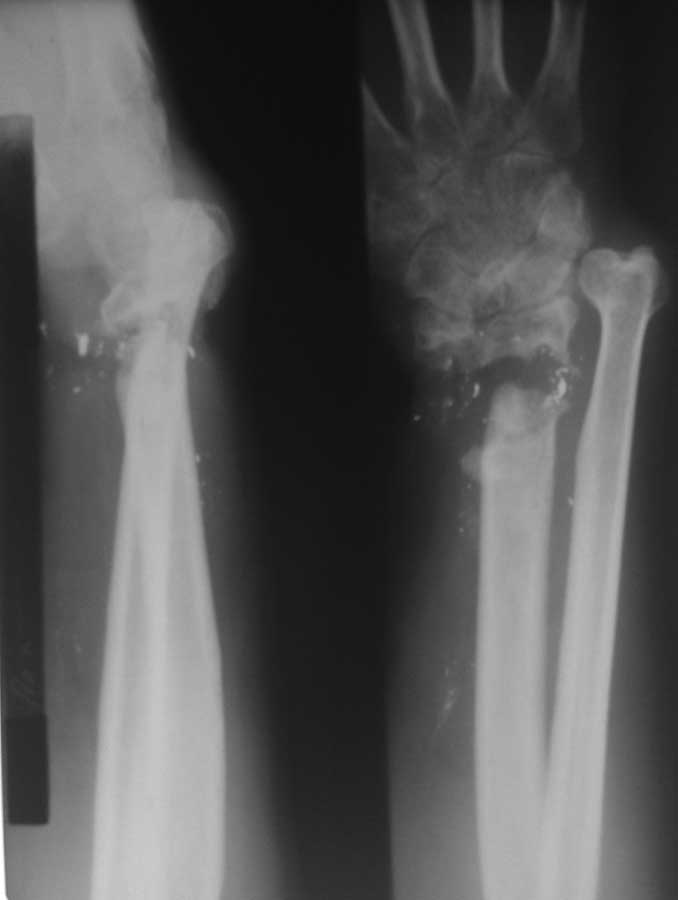

Вот дополнительные снимки

Мы предлагаем: Резекция ложного сустава в области дистального метаэпифиза лучевой кости. Артродез лучезапястного сустава. Пластика дефекта в области луча в типичном месте аутотрансплантантом из локтевой кости на сосудистой ножке. Остеосинтез пластиной. Укорочение локтевой кости. Остеосинтез пластиной.

Кто нибудь делал такого рода операции? Каков будет результат?